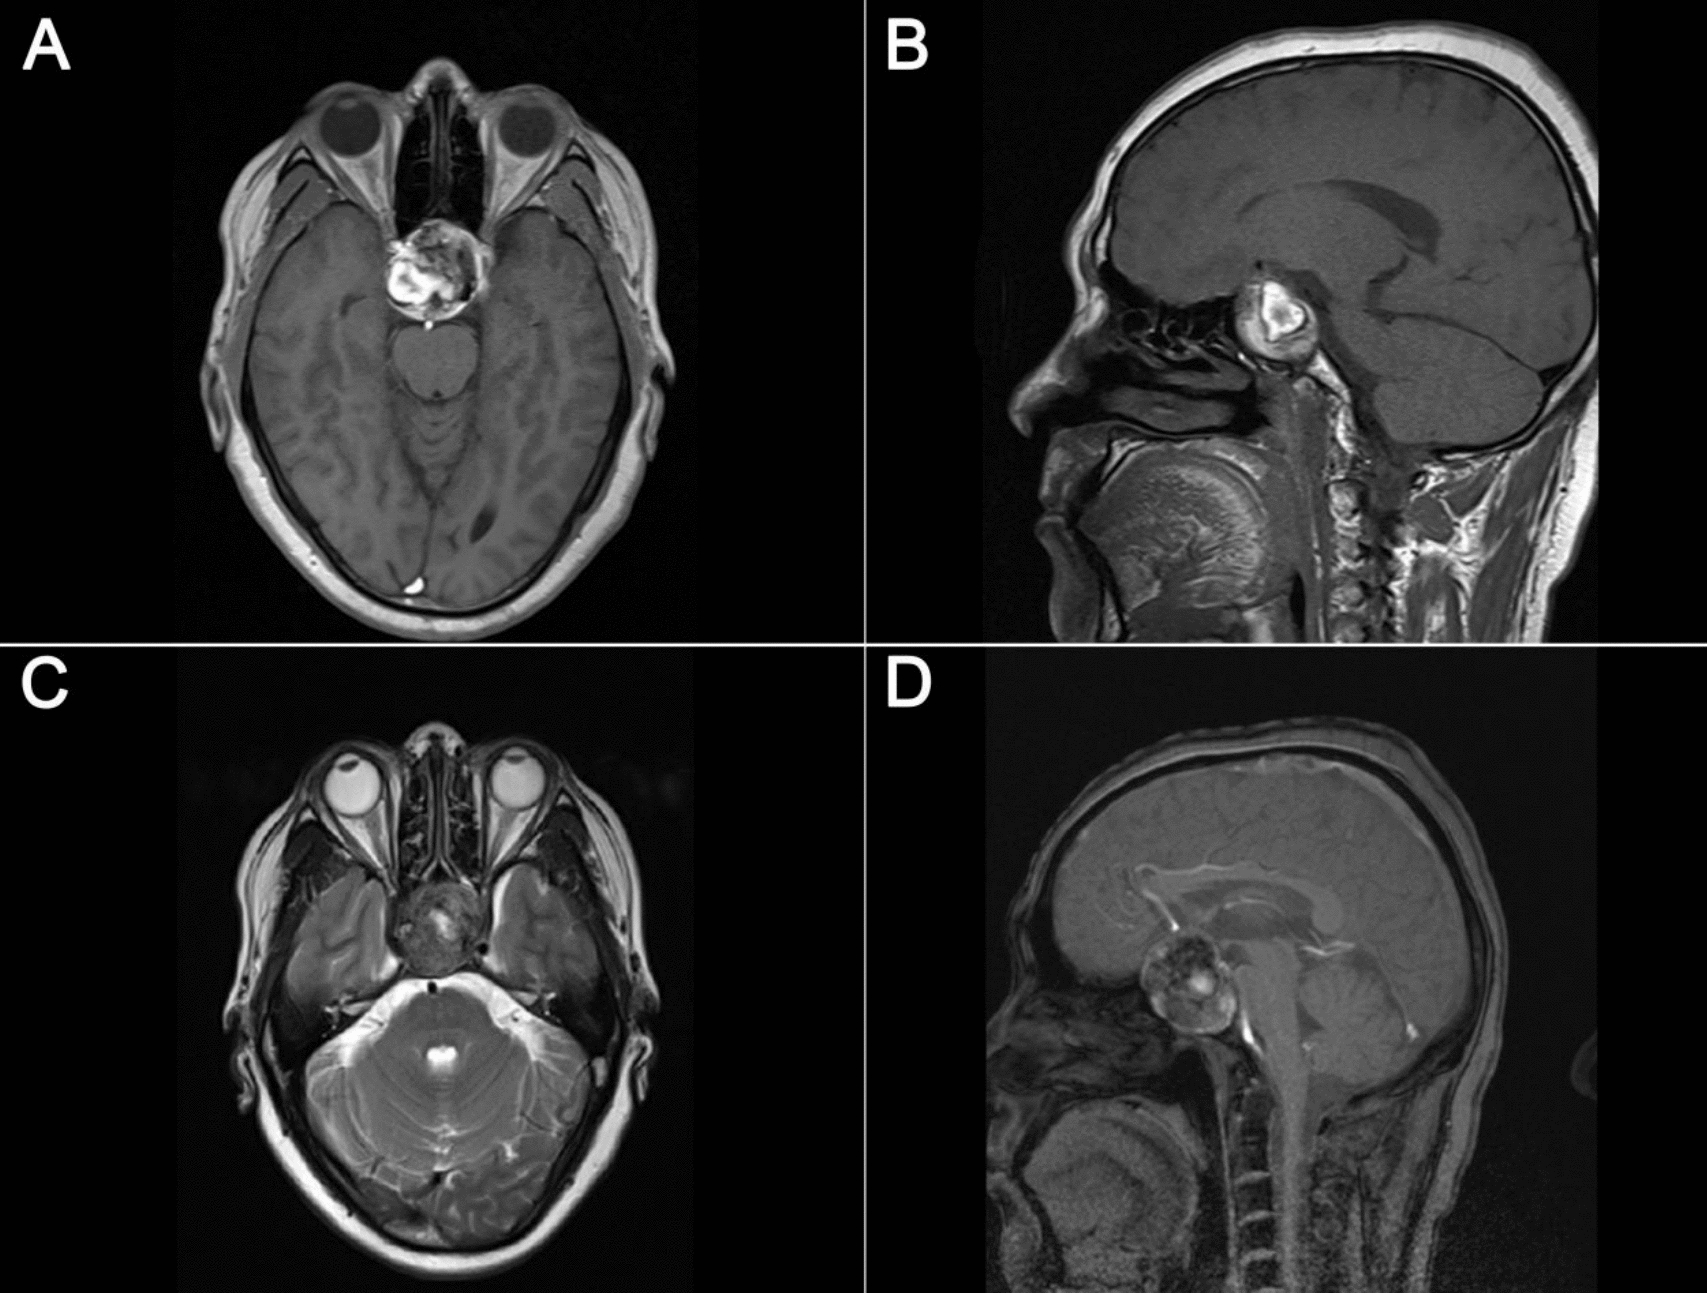

Donoho D, Zada G (2015) Imaging of central neurocytomas. Neurosurg Clin N Am 26:11–19. https://doi.org/10.1016/j.nec.2014.09.012

Ramsahye H, He H, Feng X, Li S, Xiong J (2013) Central neurocytoma: radiological and clinico-pathological findings in 18 patients and one additional MRS case. J Neuroradiol 40:101–111. https://doi.org/10.1016/j.neurad.2012.05.007